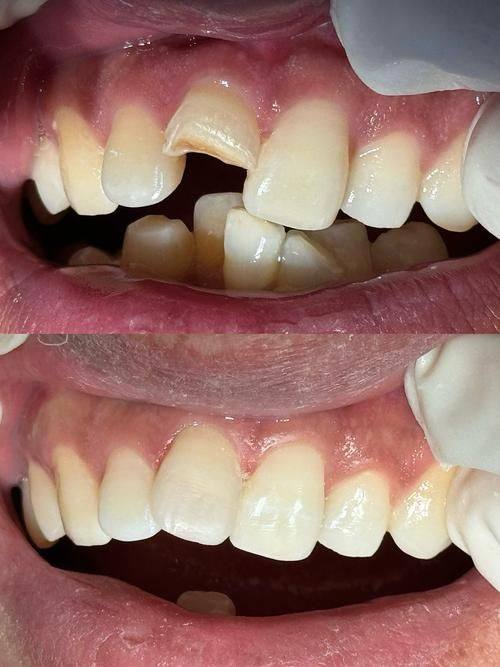

牙冠修复:可提供拉瓦、威兰德、爱尔创等品牌牙冠修复服务,针对牙齿缺失、缺损、变色等问题定制美观耐用的修复方案

西吉县雅康口腔门诊部拉瓦牙冠修复:3000元起

西吉县雅康口腔门诊部威兰德牙冠修复:2000元起

西吉县雅康口腔门诊部爱尔创牙冠修复:1500元起